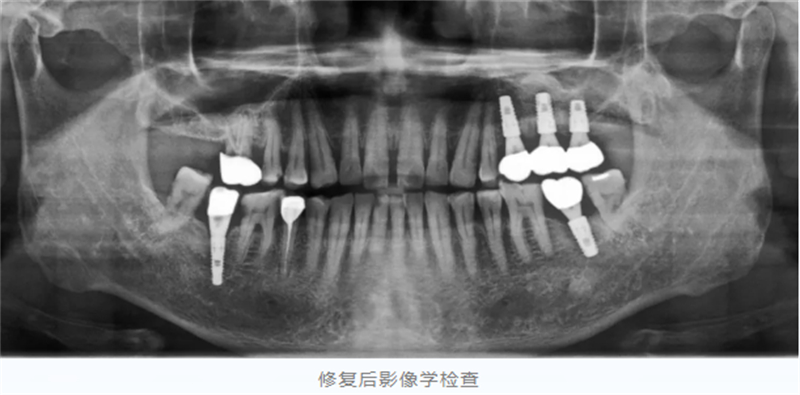

術后,任叔叔咀嚼功能得到很好恢復,他和家人心情激動,再三感謝口腔科團隊以精湛醫術幫他完成了這樁“心頭大事”。

拍攝X光片(通常每年一次):評估牙槽骨的高度和密度是否穩定,這是判斷種植體健康與否的“金標準”。